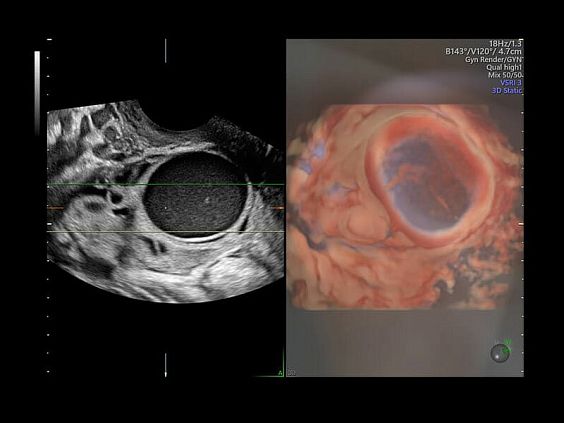

• Гинекология

• Advanced VCI (Volume Contrast Imaging) - расширенный программный пакет объемного контрастного изображения (VCI) для механических и электронных объемных датчиков:

• Проведение любой произвольной плоскости в 3D/4D (OmniView)

• Объемное контрастирование любой произвольной плоскости (OmniView+VCI)

• VOLUME CALCULATION II (VOCAL, Virtual Organ Computer Aided Analysis) – программное обеспечение для полуавтоматического определения контуров структур и расчета их объема в режиме объемной реконструкции для механических и электронных объемных датчиков

• SonoAVC (Sonography based Automated volume Count аnalysis) - программа для автоматического расчета размеров и объема анэхогенных образований/структур в режиме объемной реконструкции. Включает программу для расчета фолликулов и программу для расчета других анэхогенных структур для механических и электронных объемных датчиков

• SonoVCAD labor - программное обеспечение для исследования во втором периоде родов для механических и электронных объемных датчиков

• Усовершенствованный режим объемной визуализации с контрастированием (Volume Contrast Imaging, VCI) и опция OmniView

• Повышает контрастное разрешение и улучшает визуализацию области интереса в любой плоскости сечения, даже при исследовании структур неправильной формы.

• SonoAVC (Sonography-based Automated Volume Count) — инновационный инструмент для визуализации и измерения гипоэхогенных структур, в том числе фолликулярного аппарата и мозга плода, а также для выполнения соногистерографии.